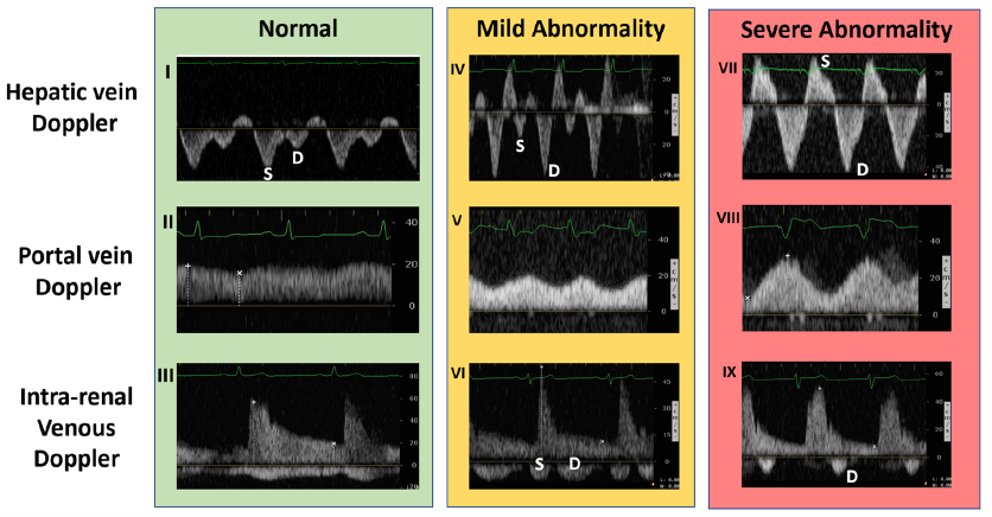

(4/x) Venous congestion is a pathologic state where high venous pressures are transmitted retrograde from the right atria into organs like the liver, brain, kidney, and bowel causing organ dysfunction.

#VEXUS or #Doppler markers of congestion are better predictors of venous congestion.

This however, (like CVP) is actually imprecise at a patient level with only moderate predictive accuracy, which is why #VEXUS uses organ level Doppler of the hepatic vein, portal vein, and intra-renal vein to predict fluid responsiveness